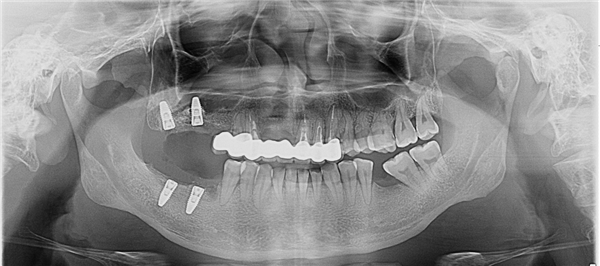

但术前的CBCT检查却发现一个棘手的问题:陈先生右上后牙一关键种植位点的牙槽骨骨高度仅有2-3mm(大概1元硬币厚度)!而常规种植体的高度通常在8mm以上,这意味着常规的种植方案无法施行。

·针对骨高度仅2-3毫米的右上后牙区,采用上颌窦外提升术,精准剥离并抬升窦底黏膜,同期植入骨粉,并顺利植入1颗4.3mm×10mm的种植体。

术后CBCT复查显示,上颌窦外提升区域的骨高度成功提升了6—7毫米,为种植体的长期稳定奠定了基础。